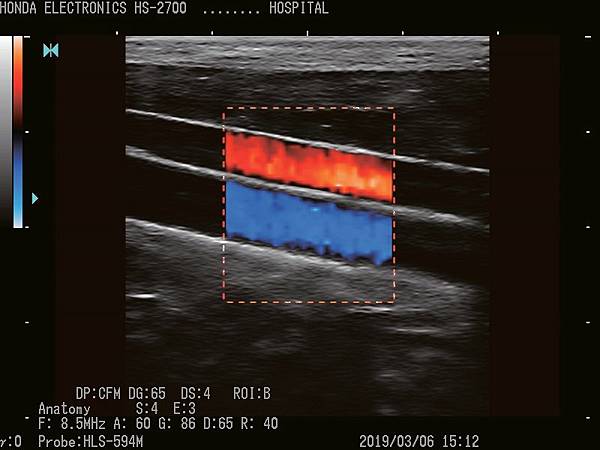

HS-2700支持CFM(彩色血流向)和PD(功率杜普勒)模式。

它們將適應廣泛的醫療應用。